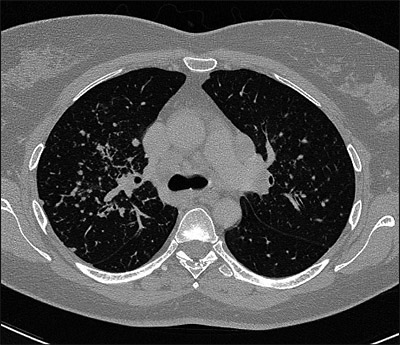

Einblicke in die Lunge

2: coronares CT Schnittbild

6: Computertomographie ohne Kontrastmittel